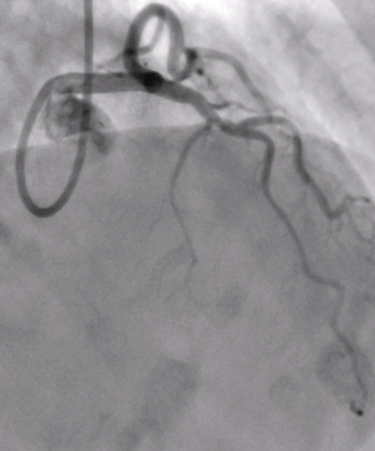

Invasive Angiography with Physiology & VasoReactivity tests

Advanced & Guidelines-Indicated State-of-the Art Invasive Diagnostics